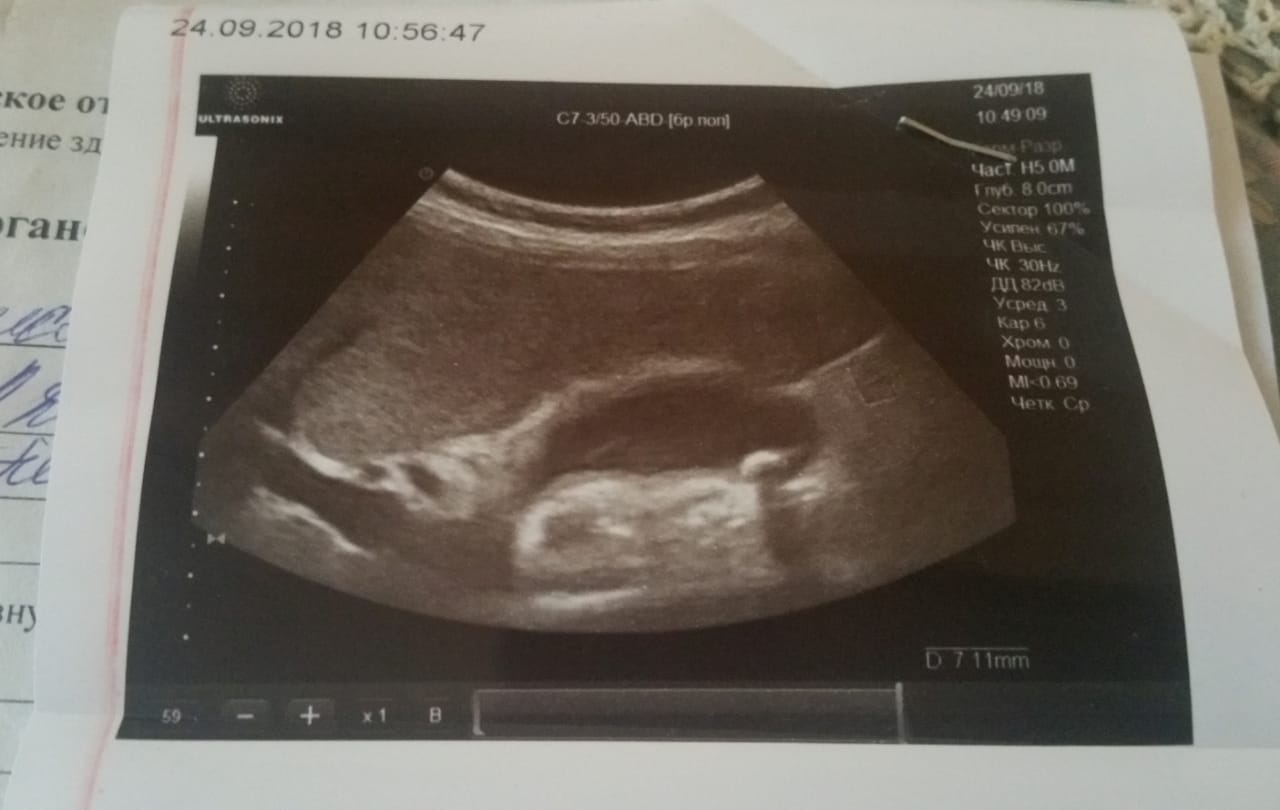

Ну и где тут цирроз??

Печень края ровные (а не бугристые или волнистые), структура однородная , размер не увеличен или не уменьшен.

Вены все нормального размера, селезёнка не увеличена. Значит печень может всю кровь в себя пропускать, не увеличивая давление и раздувая вены.

Нет никакого цирроза.

ольча, приветик, это печень? Или я что то не правильно поняла по УЗИ?!

я тоже не поняла, пока мне муж не показал, чтогде))) свехрху печень лежит, не первом плане желчный) говорит,чё дёргаешься, нормальная у тебя печень.